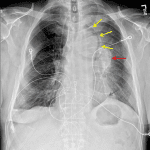

Age: 70

Sex: Male

Indication: Fever

Findings

- Left hilar mass

- Left upper lobe collapse with an aerated portion of the superior segment of the left lower lobe interposed between the atelectatic left upper lobe and the mediastinum (Luftsichel sign)

- Blunting of the right costophrenic sulcus

Diagnosis

- Left upper lobe collapse

Left hilar mass concerning for primary malignancy with associated left upper lobe collapse. Recommend chest CT for further evaluation.

Blunting of the right costophrenic sulcus which may relate to a small effusion, scarring, or overlying skin fold.